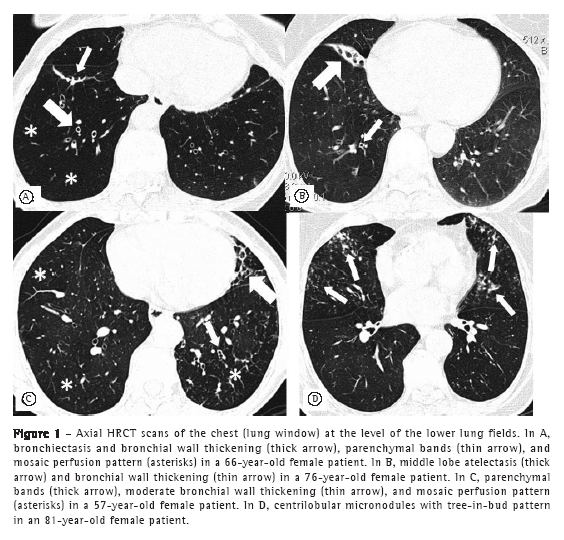

Regarding HRCT abnormalities, bronchiectasis, mosaic perfusion pattern, linear atelectasis (lobar atelectasis in one patient), and tree-in-bud pattern were significantly more common in the females in the COPD group than in those in the control group. None of the participants had panlobular emphysema. Lower lobe lesions predominated (Table 2 and Figure 1).

After age matching, parenchymal bands, bronchial wall thickening, bronchiectasis, mosaic perfusion pattern, and laminar atelectasis were found to be significantly more common in the COPD group than in the control group. As can be seen in Table 4, those abnormalities occurred predominantly in the lower lung fields (in 76.6%), having occurred in the middle lung fields in 15.6% and in the upper lung fields in 7.8%.